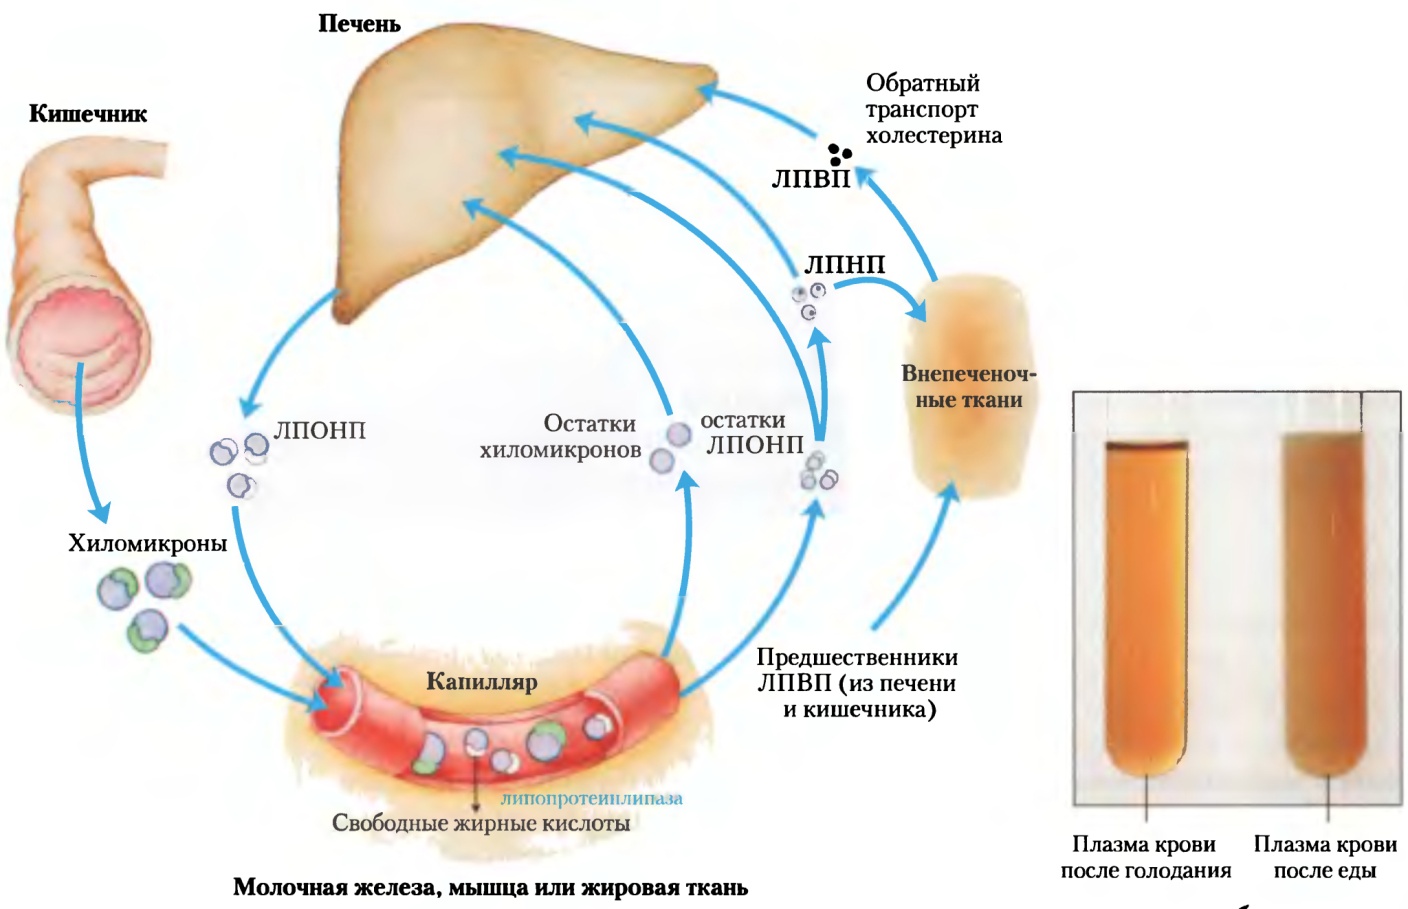

Холестерин в организме: влияние и функции (схемы и диаграммы)